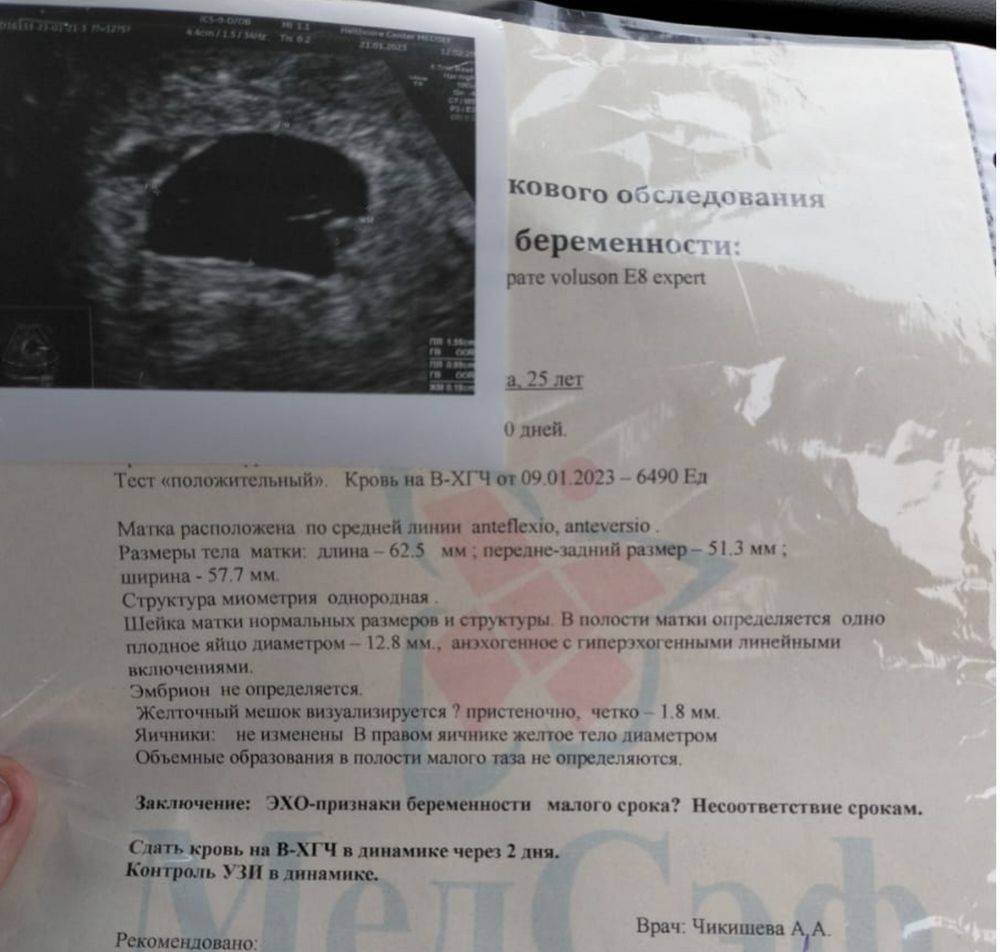

Точный диагноз анэмбрионии

Для точного диагноза анэмбрионии необходимо провести ультразвуковое исследование. Это позволит определить наличие эмбриона и его сердцебиение.

Иногда для уточнения диагноза необходимо повторить ультразвуковое исследование через несколько дней или недель. Также может потребоваться дополнительное исследование крови и других показателей здоровья женщины.